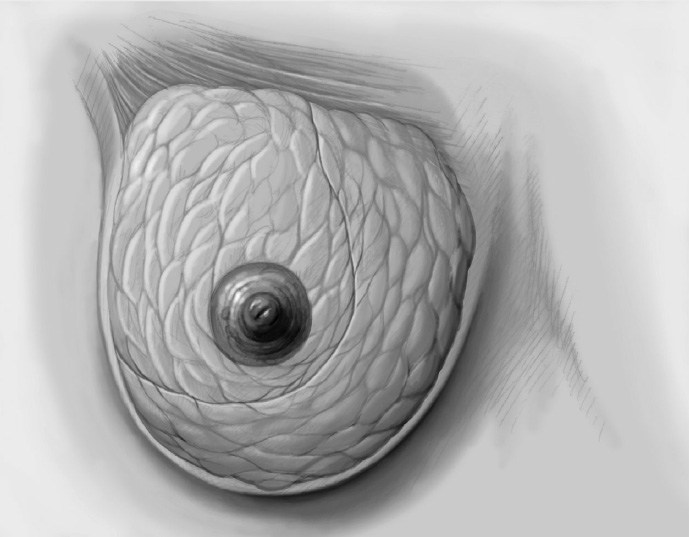

The mobilized breast lobes are rotated into the defect and approximated by interrupted sutures. Complete covering of the defect is desirable.

The skin is closed in two layers with recentering of the nipple–areola complex using interrupted sutures (Vicryl 3–0) according to the preoperative de-epithelialization pattern, which can be corrected at this time.

The skin is closed with an intracutaneous continuous monofilament suture.